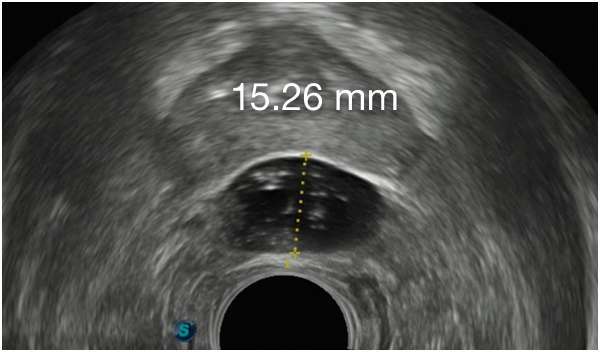

CONSISTENLY CREATE

SYMMETRICAL IMPLANTS,

FROM DAY 1

CONSISTENLY CREATE SYMMETRICAL IMPLANTS, FROM

DAY 1

First Barrigel Cases - Consecutive Patients (Same Day)

TRUS images courtesy of Daniel R. Welchons, MD

Urologist; New York, United States